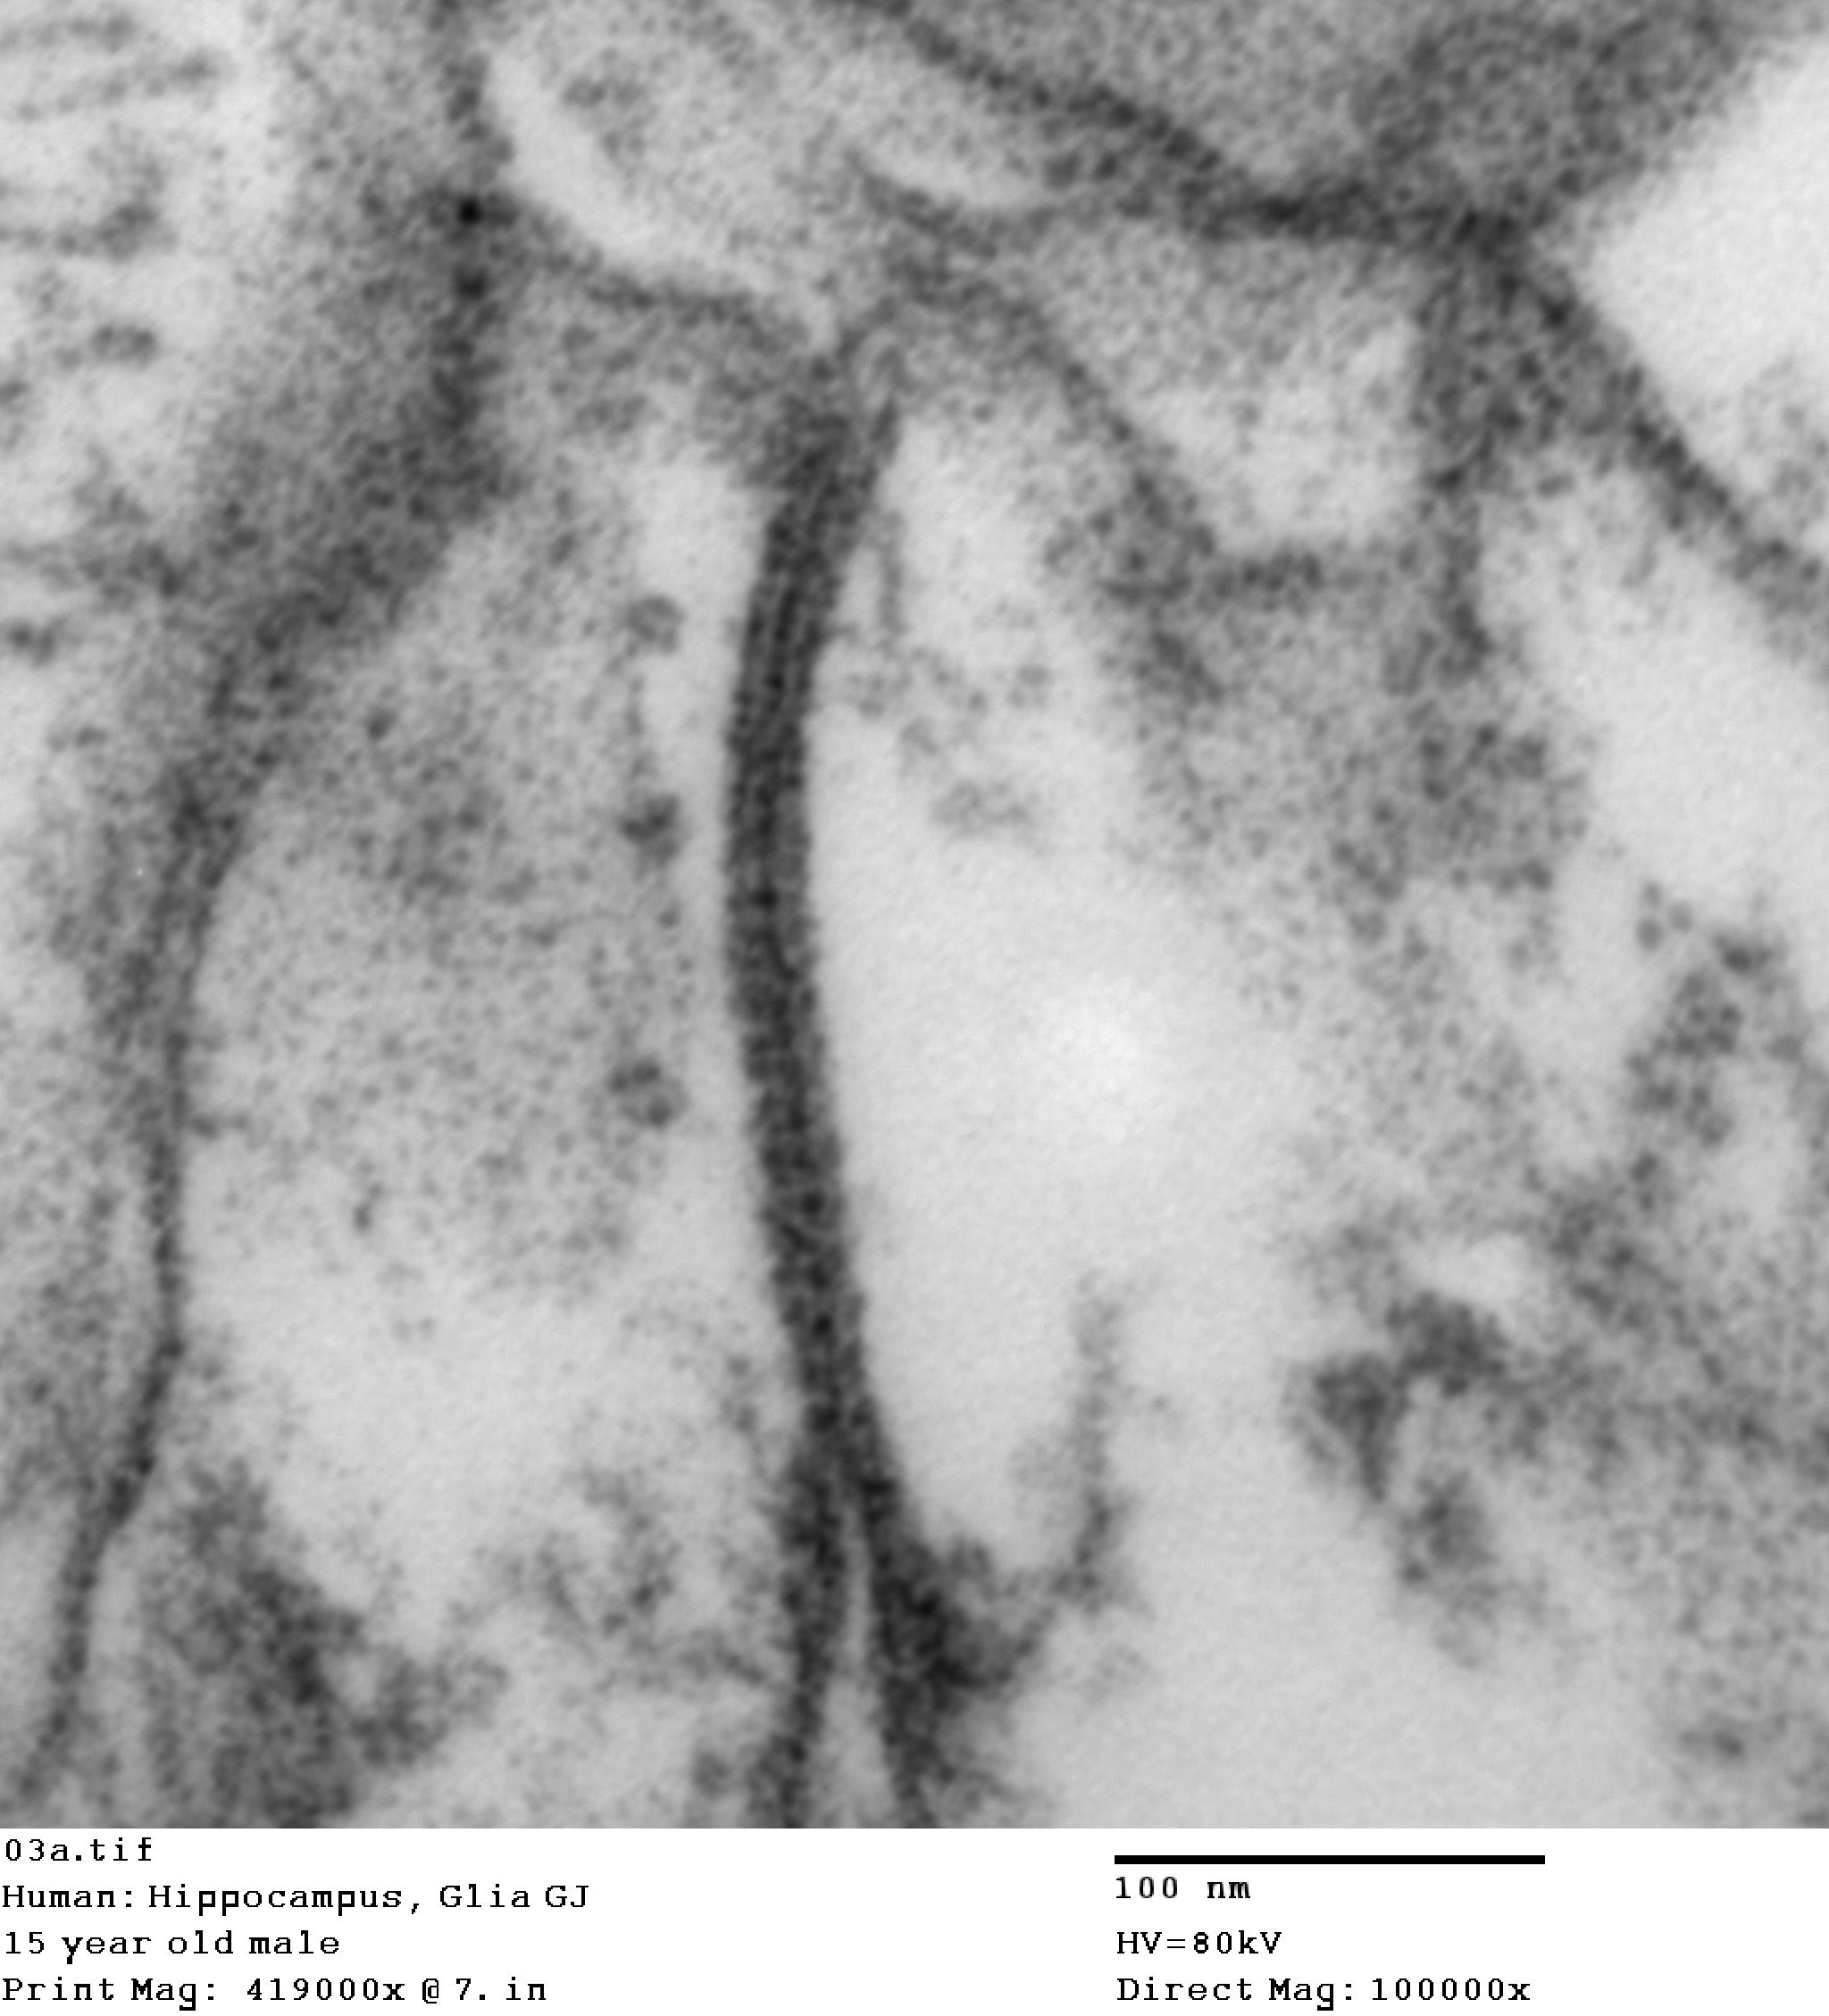

Electron Microscopy of human cortex

Gap junctions